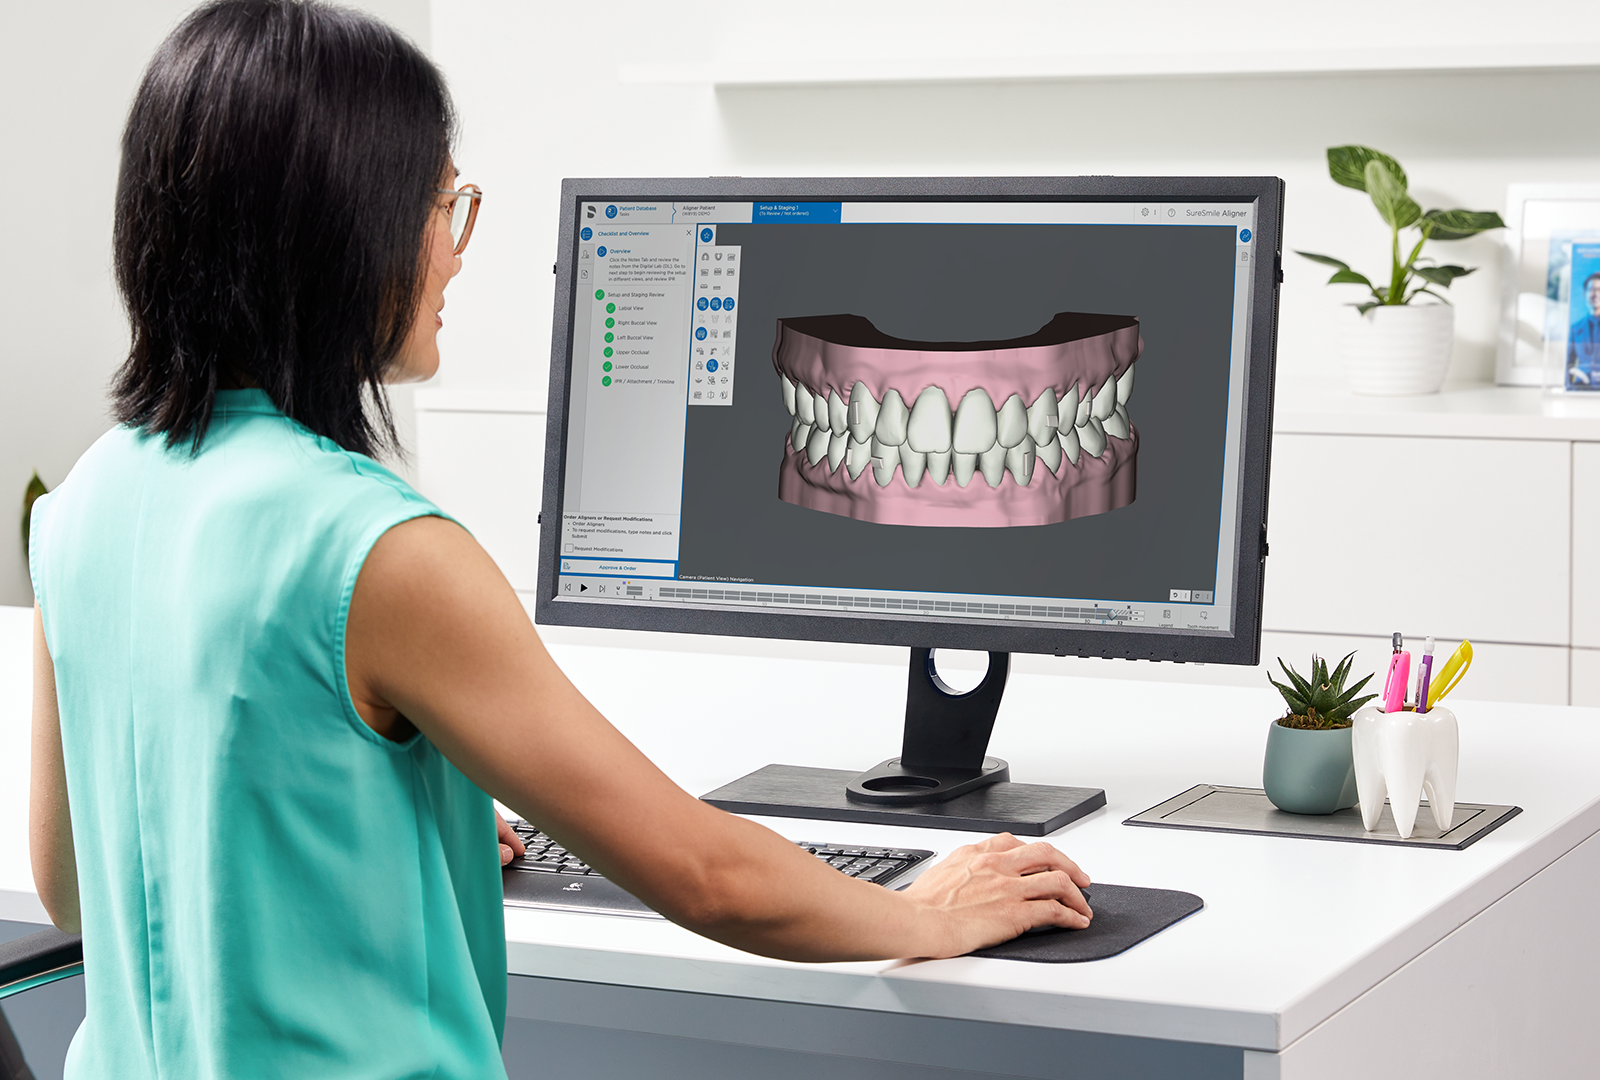

Thanks to digital dentistry, clinicians have access to groundbreaking solutions, enabling them to plan and execute all-inclusive dental treatments with unparalleled accuracy and effectiveness. This free online aligner course series helps dental professionals become more confident and comfortable using clear aligner therapy (CAT), which has become a popular choice for patients looking for a less intrusive orthodontic option. In this series, learners will gain an understanding of the biomechanics of therapeutic tooth movement, efficient treatment methodologies, and how to diagnose and treat cases.

- Reviewing and finalizing digital treatment plans and communicating them to patients

Procedure-Based

The intermediate-level courses are ideal for clinicians with an established understanding of the basics of clear aligner therapy or those looking to refine their skills. These five interactive courses are designed to provide clinicians with a comprehensive understanding of identifying and treating aligner case types efficiently and predictably. At the end of the Procedure-Based courses, you are encouraged to move forward to our advanced courses, the Mastery courses.

Mastery

These two advanced-level courses are ideal for experienced clinicians with an established understanding of clear aligner therapy. These interactive courses will teach clinicians how to diagnose and treat more complex case types, including interdisciplinary cases. Participants will also learn about auxiliaries and adjuncts to control root and bodily movements better. By the end of the Mastery courses, participants will have the confidence to incorporate CAT into their practice.